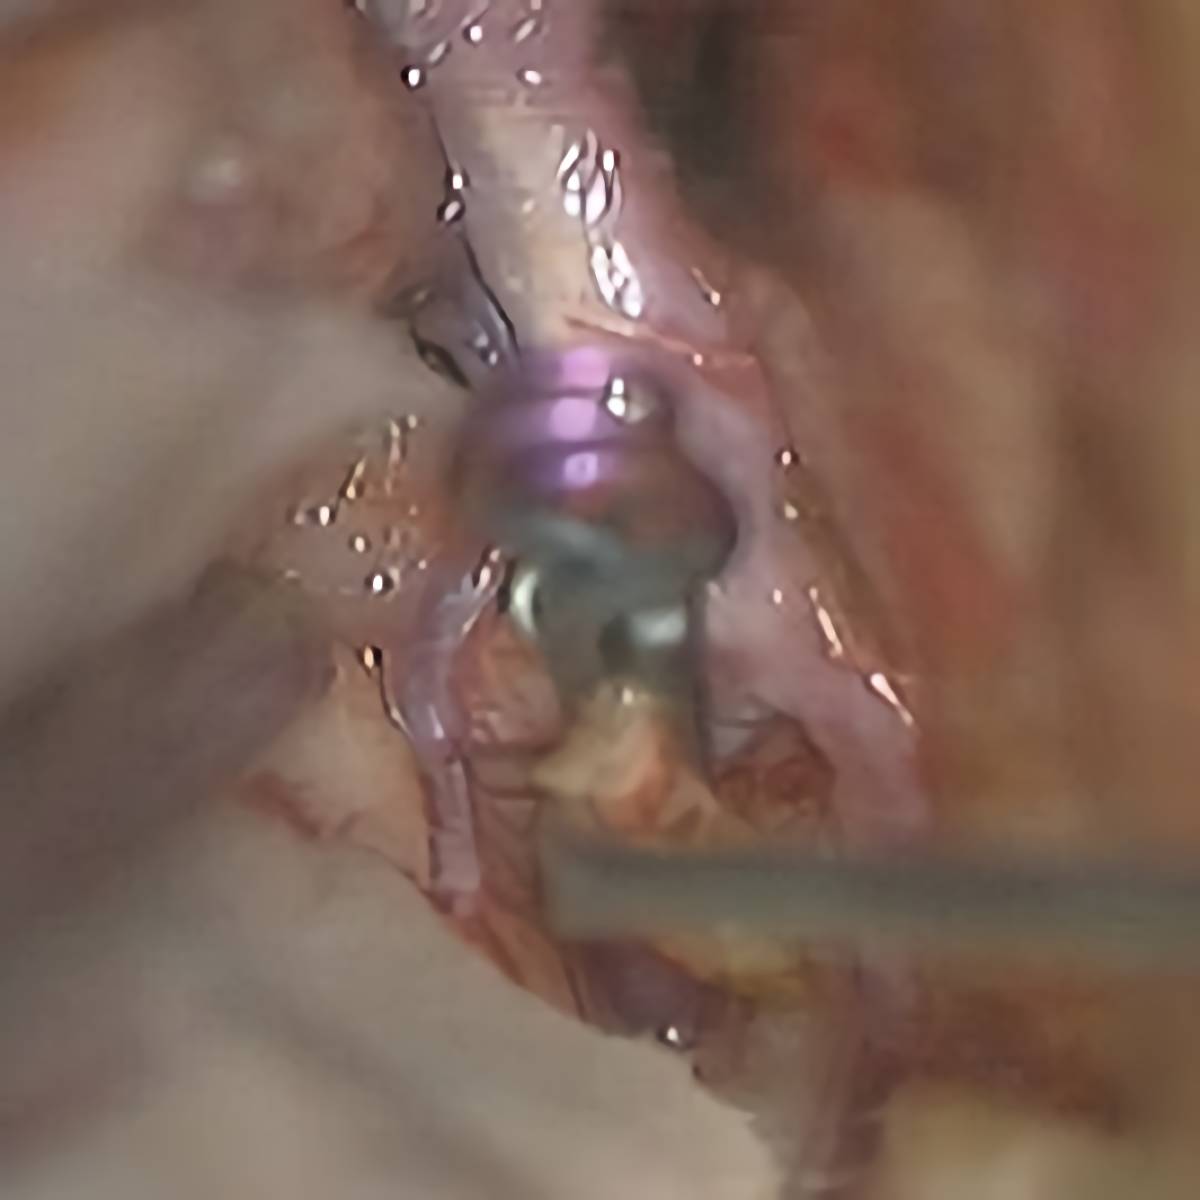

クリップ前

クリップ後

術後血管撮影

65

'18年5月

70代

右後交通動脈瘤

クリッピング術